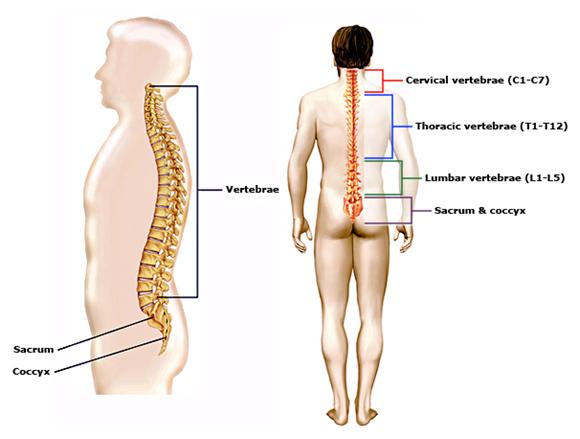

Позвонок Th10: анатомия и фото медицинских иллюстраций